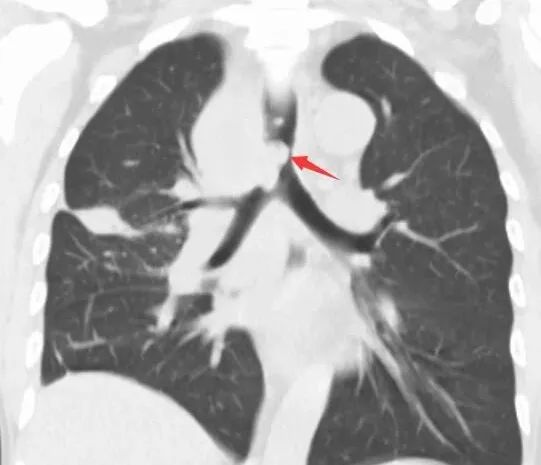

支架置入前(图 1 为 CT 冠状位,红色箭头提示肿物阻塞气道;图 2 为 CT 纵隔窗,白色箭头所指为气道肿物;图 3 为气管镜下图像,红色箭头所指为气道肿物。)

为充分保障患者安全,治疗团队决定对患者先用 ECMO 来改善氧合,之后再进行手术。重症医学科团队有条不紊地为患者进行双侧股静脉置管,连接人工肺管路,使患者血氧饱和度维持在 95% 以上。而在患者的另一边,呼吸介入团队快速插入硬质支气管镜,镜下可见患者气管下段气管已被完全堵塞。